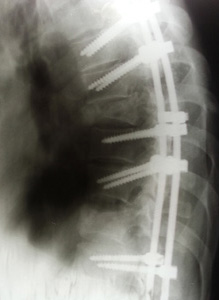

Diese Erfahrung wird vielfach von Illegalen berichtet. Man kann sich nicht beschweren, da die lokalen Behörden an diesem mafiosen System beteiligt sind. Das ist jedoch noch nicht alles. Die Illegalen arbeiten auf Baustellen, an denen die grundlegenden Sicherheitsmaßnahmen am Arbeitsplatz fehlen. Ions Baustelle hatte ein improvisiertes Gerüst, welches plötzlich zusammenbrach. Er stürzte aus erheblicher Höhe zu Boden, wobei er mehrere Wirbelfrakturen erlitt.

Als er in einem der Moskauer Krankenhäuser aufgenommen wurde, lag er für 10 Tage auf einer Matratze auf dem Boden. Außer Schmerzmittel erhielt er keine weitere Hilfe. Seine Familie hat lange Zeit gekämpft, um das Geld für den Rücktransport nach Moldau zu finden. Victor Ungureanu, ein Arzt, mit dem wir seit Jahren in der traumatologischen Klinik in Chisinau zusammenarbeiten, teilte mit, dass er einen solchen Fall bislang nicht gesehen habe. Die Tatsache, dass ein Mann solange leidet und noch am Leben ist, sei nur durch ein Wunder zu erklären.

Eine sofortige Operation scheiterte an der Tatsache, dass Ions Rücken und das Gesäß völlig vereitert waren und somit erst einmal antiseptische Maßnahmen ergriffen werden mussten. Erst danach hatten wir die Möglichkeit weitere Operationen zu veranlassen. Dr. Ungureanu stellt fest, dass Ion in seinen Beinen noch teilweise Empfindungen verspürt. Er hofft, durch weitere Operationen Erfolge erreichen zu können. Allerdings sind die Aufenthalte in moldauischen Kliniken nicht kostenlos.